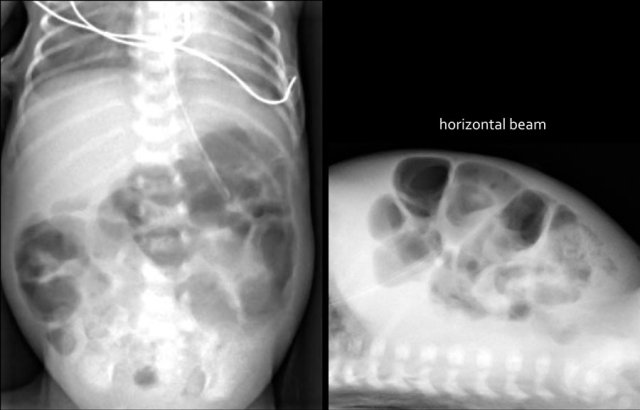

Here images of a neonate who developed NEC.

At this early stage the radiograph only shows non-specific bowel dilatation.

At this stage you cannot make the diagnosis.